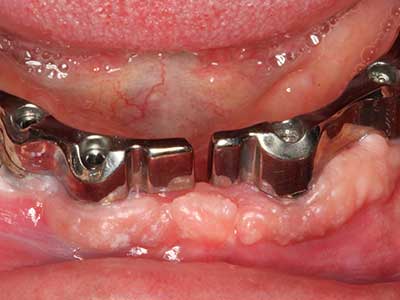

Костната тъкан е не само минерализирана структура, тя съдържа и съществено количество колагенови влакна. Това означава, че тя има не само добра компресивна сила, но и известна степен на гъвкавост, която може да се възприеме като предимство при извършване на костна аугментация. В класическата процедура по разширяване чрез костно разделяне, атрофиралият алвеоларен гребен е разделен надлъжно и внимателно разширен след достигане на подходящата остеотомна дълбочина (Фиг. 13-16), в идеалния случай без допълнително отстраняване на периостеума (Brugnami, Caiazzo et al. 2014, Stricker, Fleiner et al. 2014). Системите с винт и пластини с увеличаване на разстоянието при разширяване са доказали ефективността си при разделяне на двете костни ламели, оставайки под прага на фрактурите. В общи линии, оставащата ширина на костта от поне 3–4 mm е задължителна (Chiapasco, Zaniboni et al. 2006), за да се гарантира добра гъвкавост и достатъчно костно покритие за бъдещото поставяне на импланти. Ако е необходимо, вертикалната остеотомия на едната или двете страни може да подобри гъвкавостта. Комбинацията с допълнителни техники за аугментация, особено в букалната страна, е описана като алтернатива на класическата техника.

Процедурата по разделяне е атравматична и няма голяма загуба на пространство, използвайки пиезотриони, и няма значителна разлика между импланти в разделени челюсти и импланти в алвеоларния гребен без костен дефицит (Chiapasco, Zaniboni et al. 2006, Danza, Guidi et al. 2009). Въпреки това, важно е да има достатъчно и продължително охлаждане, особено при ограничено и дълбоко разделяне, за да се избегне термичен стрес в апикално-остеотомните зони.